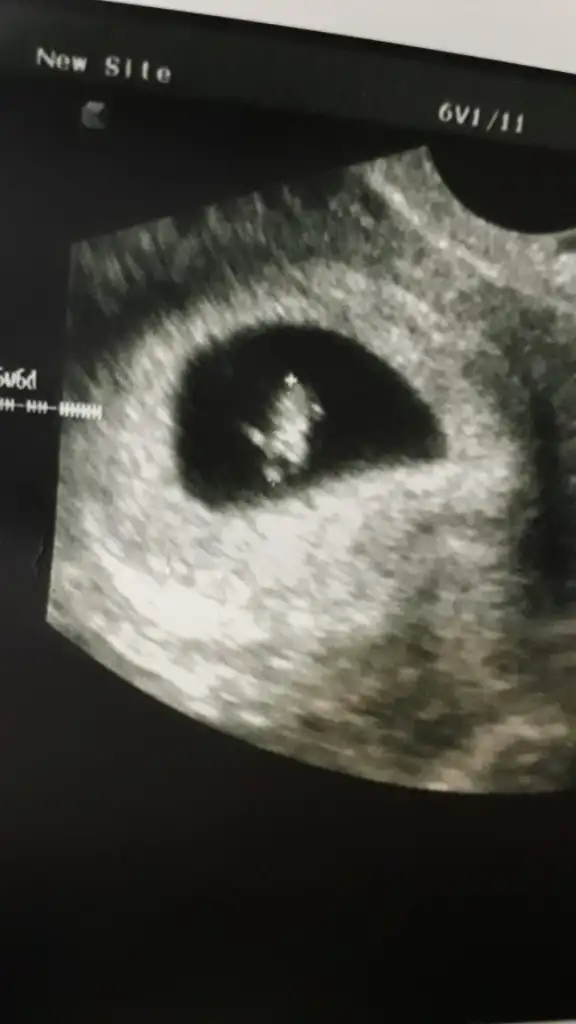

Emin olmamakla birlikte erkekH Hulyabozkurt merhababenimkini de yorumlayabilir misiniz rica etsem :) 7 haftalık vajinal ultrason Eki Görüntüle 3061369 Eki Görüntüle 3061370

8 haftalık karından ultrason da bebek sağda ama plesanta solda bu durumda erkek olması gerekiyo Bi daha ki kontrolümde kesinleşecek dedi doktor

hayırlısı olsun benimde en son 8+5 resmim bu yeterki sağlıklı koşunlarda insan yine de merak ediyor teşekkür ederim

Erkeğe benziyo plesanta solda sankihayırlısı olsun benimde en son 8+5 resmim bu yeterki sağlıklı koşunlarda insan yine de merak ediyor teşekkür ederim